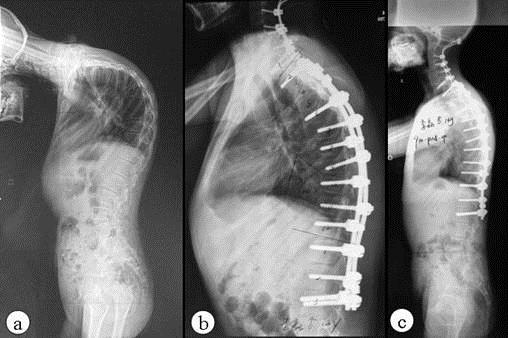

QZ16030094 姓名:陈先生 性别:男 年龄:32岁

- 病情

AS ①晚期 ②重度 病史:5年+

- 治疗

治疗后骶髂关节疼痛消失,腰椎前屈、背伸侧弯活动自如,膝关节无压痛感,复查血沉、C反应蛋白、等各项检查均已达到临床康复的标准。